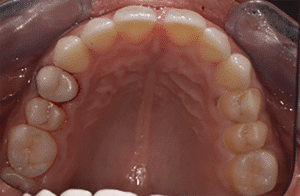

Mme AB vient en consultation pour deux raisons. La première est une douleur intense à chaque fois qu’elle boit ou mange froid. La deuxième est l’apparence de son sourire. Elle trouve que ses dents ont « raccourci » et qu’elles « s’effritent ». C’est devenu un complexe handicapant. À L’examen clinique on observe (Fig.1a, b, c, d, e) une usure vestibulaire de toutes les dents : plus prononcée au maxillaire et assez légère sur les incisives mandibulaires, une classe III canine et molaire droite, une classe I canine et molaire gauche avec une légère déviation des milieux et une usure importante des faces palatines du bloc IC maxillaire ainsi que des faces occlusales de 16 et 26. On constate aussi que les faces occlusales des autres dents sont moins touchées en apparence. On observe que les amalgames de 36 et 48 sont en relief par rapport à la dent support. Il est raisonnable de supposer qu’à l’origine ils devaient obturer une cavité et donc être à l’intérieur de la dent. Ceci témoigne donc aussi d’une forte usure sur 36 et 46. On observe enfin que les courbes de Spee sont complètement plates.

Fig.1a, b, c, d, e : Examen clinique.

Fig.1b.

Fig.1c.

Fig.1d.

Fig.1e.